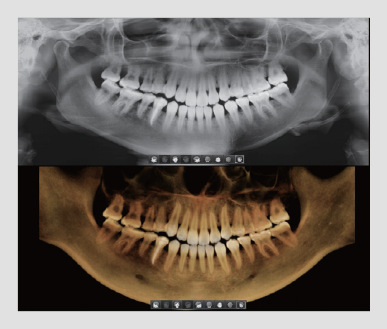

UNA TOMA, DOS IMÁGENES

Un escaneo con Smart Plus no solamente le brinda una imagen CT, sino también una imagen Auto Pano.

Esto significa que los pacientes que requieran ambas imágenes no se sometan a dos radiografías. Ambas imágenes CT y Auto Pano se muestran dentro de la función Over View

2D Y 3D EN UN VISOR

La visualización de imágenes 2D y 3D juntas proporcionan muchos beneficios. No es necesario utilizar dos programas de software diferentes y la función de un visor representa un aspecto profesional para sus pacientes.

Este diseño ayuda a los pacientes a comprender mejor las imágenes, lo que eventualmente dará como resultado un aumento de aceptación.